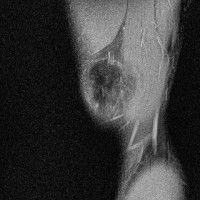

무릎 mri 간단히 봐주실 수 있으시나요 ㅠㅠ

안녕하세요 8년전 십자인대 수술하고 최근 무리한 운동에 무릎 불편감이 생겨서

mri 찍었습니다.

진단결과는 첫 찍은 병원에서 활액막염 이라는 진단을 받았습니다. 혹시 봐주실 수 있으실까요?

올라온 MRI가 단편적이라서 정확한 진단에 어려움이 있지만 십자인대에는 큰 이상이 있지는 않은것 같으며, 무릎관절내 물이 있는 것으로 보아 활액막염의 진단이 맞을 것 같습니다.

하지만 단편적인 영상이기 때문에 촬영병원에서 정확한 판독지 등을 받으시는 것이 좋겠습니다.